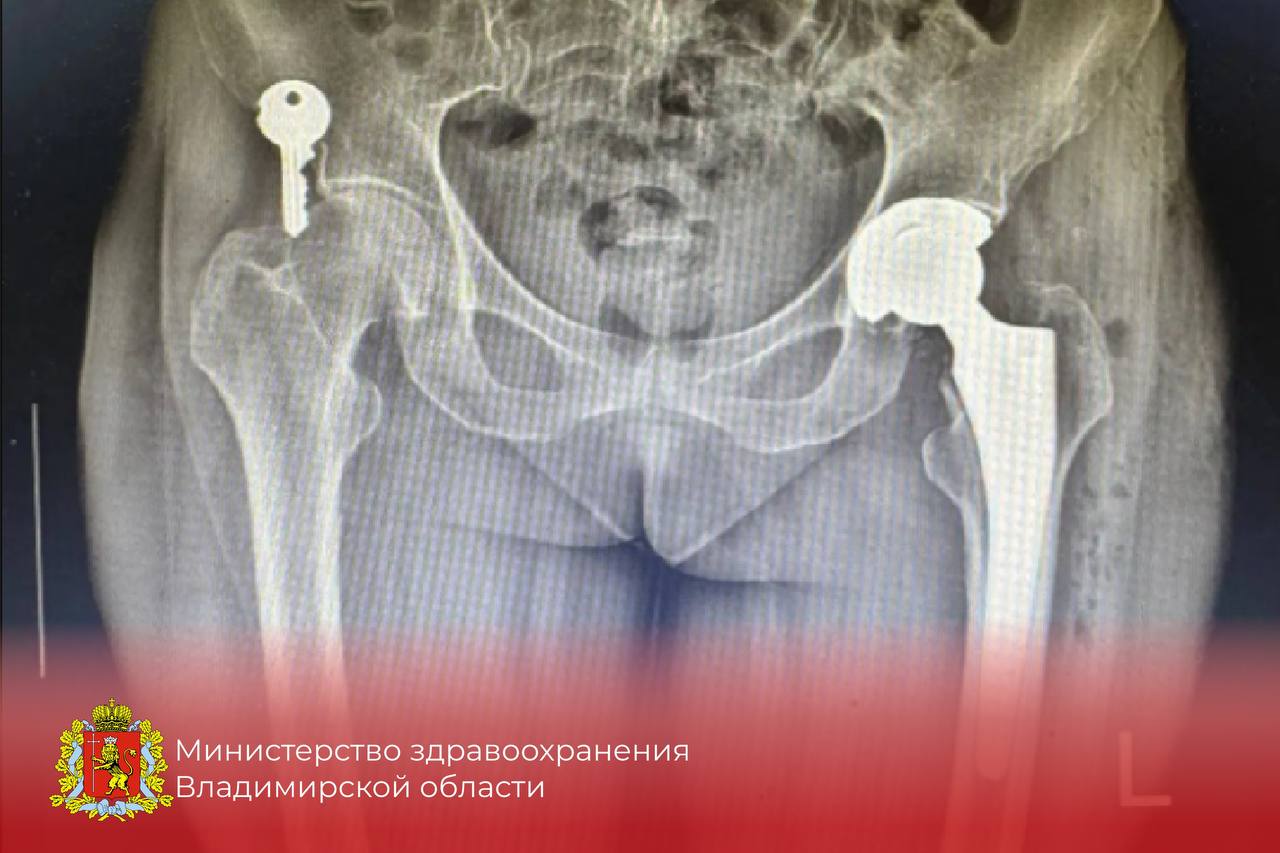

Ковровские врачи освоили передовые методы лечения переломов тазобедренного сустава

По состоянию на конец 2025 года в травматологическом отделении уже проведено свыше 10 операций по установке эндопротезов, что говорит о растущем опыте медицинского персонала и повышении уровня оказания помощи.